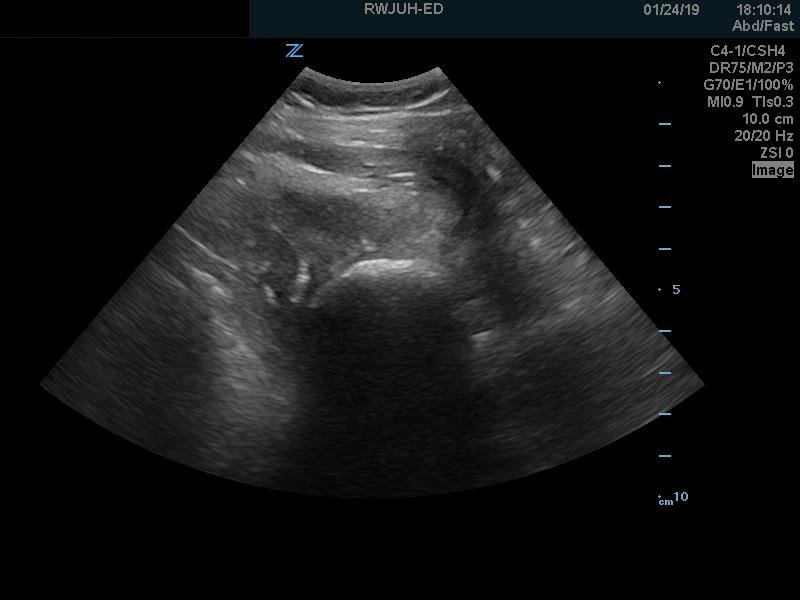

Bedside ultrasound with the transducer placed on the posterior right shoulder revealed an anterior dislocation of the right humerus. This is evident by displacement of the humeral head further away from the posteriorly placed ultrasound transducer, and appears deep to the glenoid cavity. In a posterior shoulder dislocation, the humeral head would appear closer to the transducer (and the near field of the ultrasound image) than the glenoid. Note that a hypoechoic, heterogeneous fluid collection is within the joint space, compatible with a hematoma. A right shoulder X-ray confirmed the anterior dislocation with no evidence of fracture. Under direct ultrasound guidance the glenohumeral joint space was injected with 10 mL of 2% lidocaine as an intraarticular anesthetic block. The right shoulder was reduced using continual traction. Post-reduction ultrasound demonstrated a successful shoulder reduction, depicted by the humeral head being relocated to its anatomical location, adjacent to the glenoid cavity, as noted on the ultrasound image. A hematoma remains present within the joint space. Successful shoulder reduction was further confirmed by X-ray. The patient’s arm was placed in a sling and she was discharged home with orthopedics follow-up.

Ultrasound guided intra-articular joint injections are best performed with the linear or curvilinear probe. With the probe on the patient’s lateral or posterior shoulder, locate the humeral head and the glenoid cavity. Determine the depth of the space and select a needle long enough to reach the cavity. Utilizing sterile technique, first place superficial local anesthetic. Then, advance the needle into the glenohumeral joint space and inject 10 to 20 mL of a local anesthetic, typically 1 or 2% plain lidocaine. An increase in anechoic space may be visible as the anesthetic is injected. The effect of the anesthetic should be active in about ten minutes.2,12